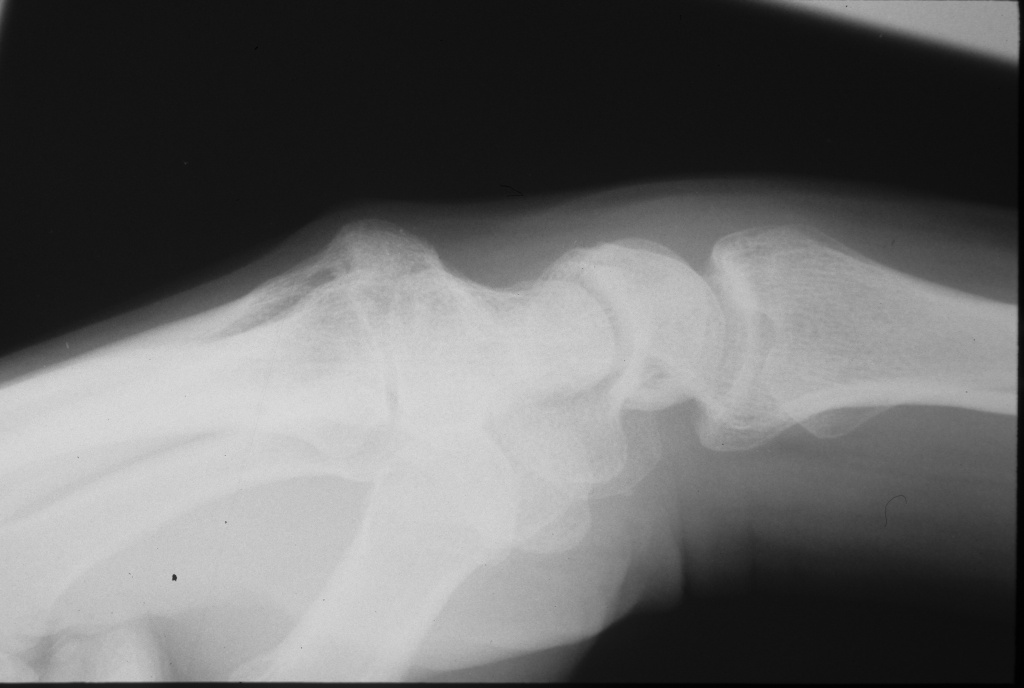

Lateral clenched fist xray tangential view profiles the prominence, here with an exostosis of the metacarpal base.